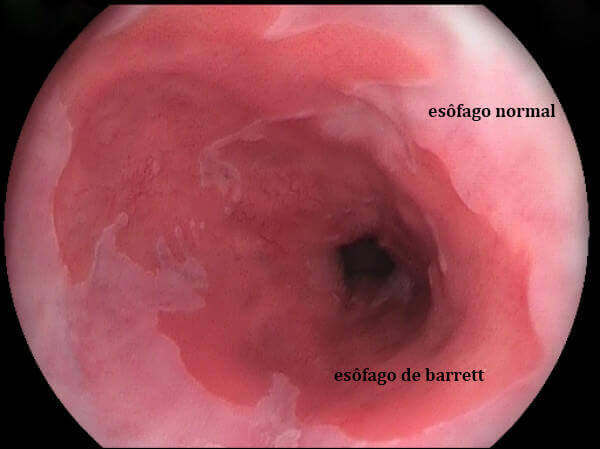

O refluxo contínuo e por longos períodos pode provocar mudança do epitélio escamoso do esôfago que é substituído pelo epitélio colunar intestinal (mais resistente). Esta alteração no epitélio (camadas de células da mucosa esofágica) é chamada de Esôfago de Barrett. Esta é uma das complicações mais sérias da DRGE, porque pode evoluir para adenocarcinoma de esôfago (câncer). O paciente que tem esôfago de Barrett tem chance 30 a 40 vezes maior de ter câncer de esôfago do que a população normal.